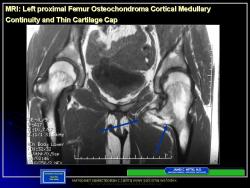

Иллюстрации из литературных источников.

Приложения:

14.N.Slayd15.JPG15.N.Slayd16.JPG16.N.Slayd17.JPG17.N.Slayd18.JPG18.N.Slayd19.JPG19.N.Slayd20.JPG1.1.Slayd20.JPG2.2.Slayd21.JPG3.3.Slayd22.JPG210.OH_.Slayd25.JPG